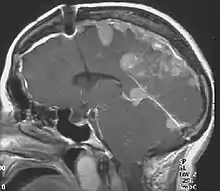

The so-called acoustic neuroma of NF2 is in fact a schwannoma of the nervus vestibularis, or vestibular schwannoma. The misnomer of acoustic neuroma is still often used. The vestibular schwannomas grow slowly at the inner entrance of the internal auditory meatus (meatus acousticus internus). They derive from the nerve sheaths of the upper part of the nervus vestibularis in the region between the central and peripheral myelin (Obersteiner-Redlich-Zone) within the area of the porus acousticus, 1 cm from the brainstem.

NF2 is a genetically transmitted condition. Diagnosis is most common in early adulthood (20–30 years); however, it can be diagnosed earlier. NF2 can be diagnosed due to the presence of a bilateral vestibular schwannoma, or an acoustic neuroma, which causes a hearing loss that may begin unilaterally.[15] If a patient does not meet this criterion of diagnosis, they must have a family history of NF2, and present with a unilateral vestibular schwannoma and other associated tumors (cranial meningioma, cranial nerve schwannoma, spinal meningioma, spinal ependymomas, peripheral nerve tumor, spinal schwannoma, subcutaneous tumor, skin plaque). This being said, more than half of all patients diagnosed with NF2 do not have a family history of the condition.[15] Although it has yet to be included into clinical classification, peripheral neuropathy, or damage to the peripheral nerves, which often causes weakness, numbness and pain in the hands and feet, may also lead to a diagnosis of NF2. In children, NF2 can present with similar symptoms, but generally causes "visual disturbances (cataracts, hamartomas), skin tumors, mononeuropathhy (facial paresis, drop foot), symptomatic spinal cord tumors, or non-vestibular intracranial tumors".[15]

Bilateral vestibular schwannomas are diagnostic of NF2.[16]

- Detection of bilateral acoustic neuroma by imaging-procedures